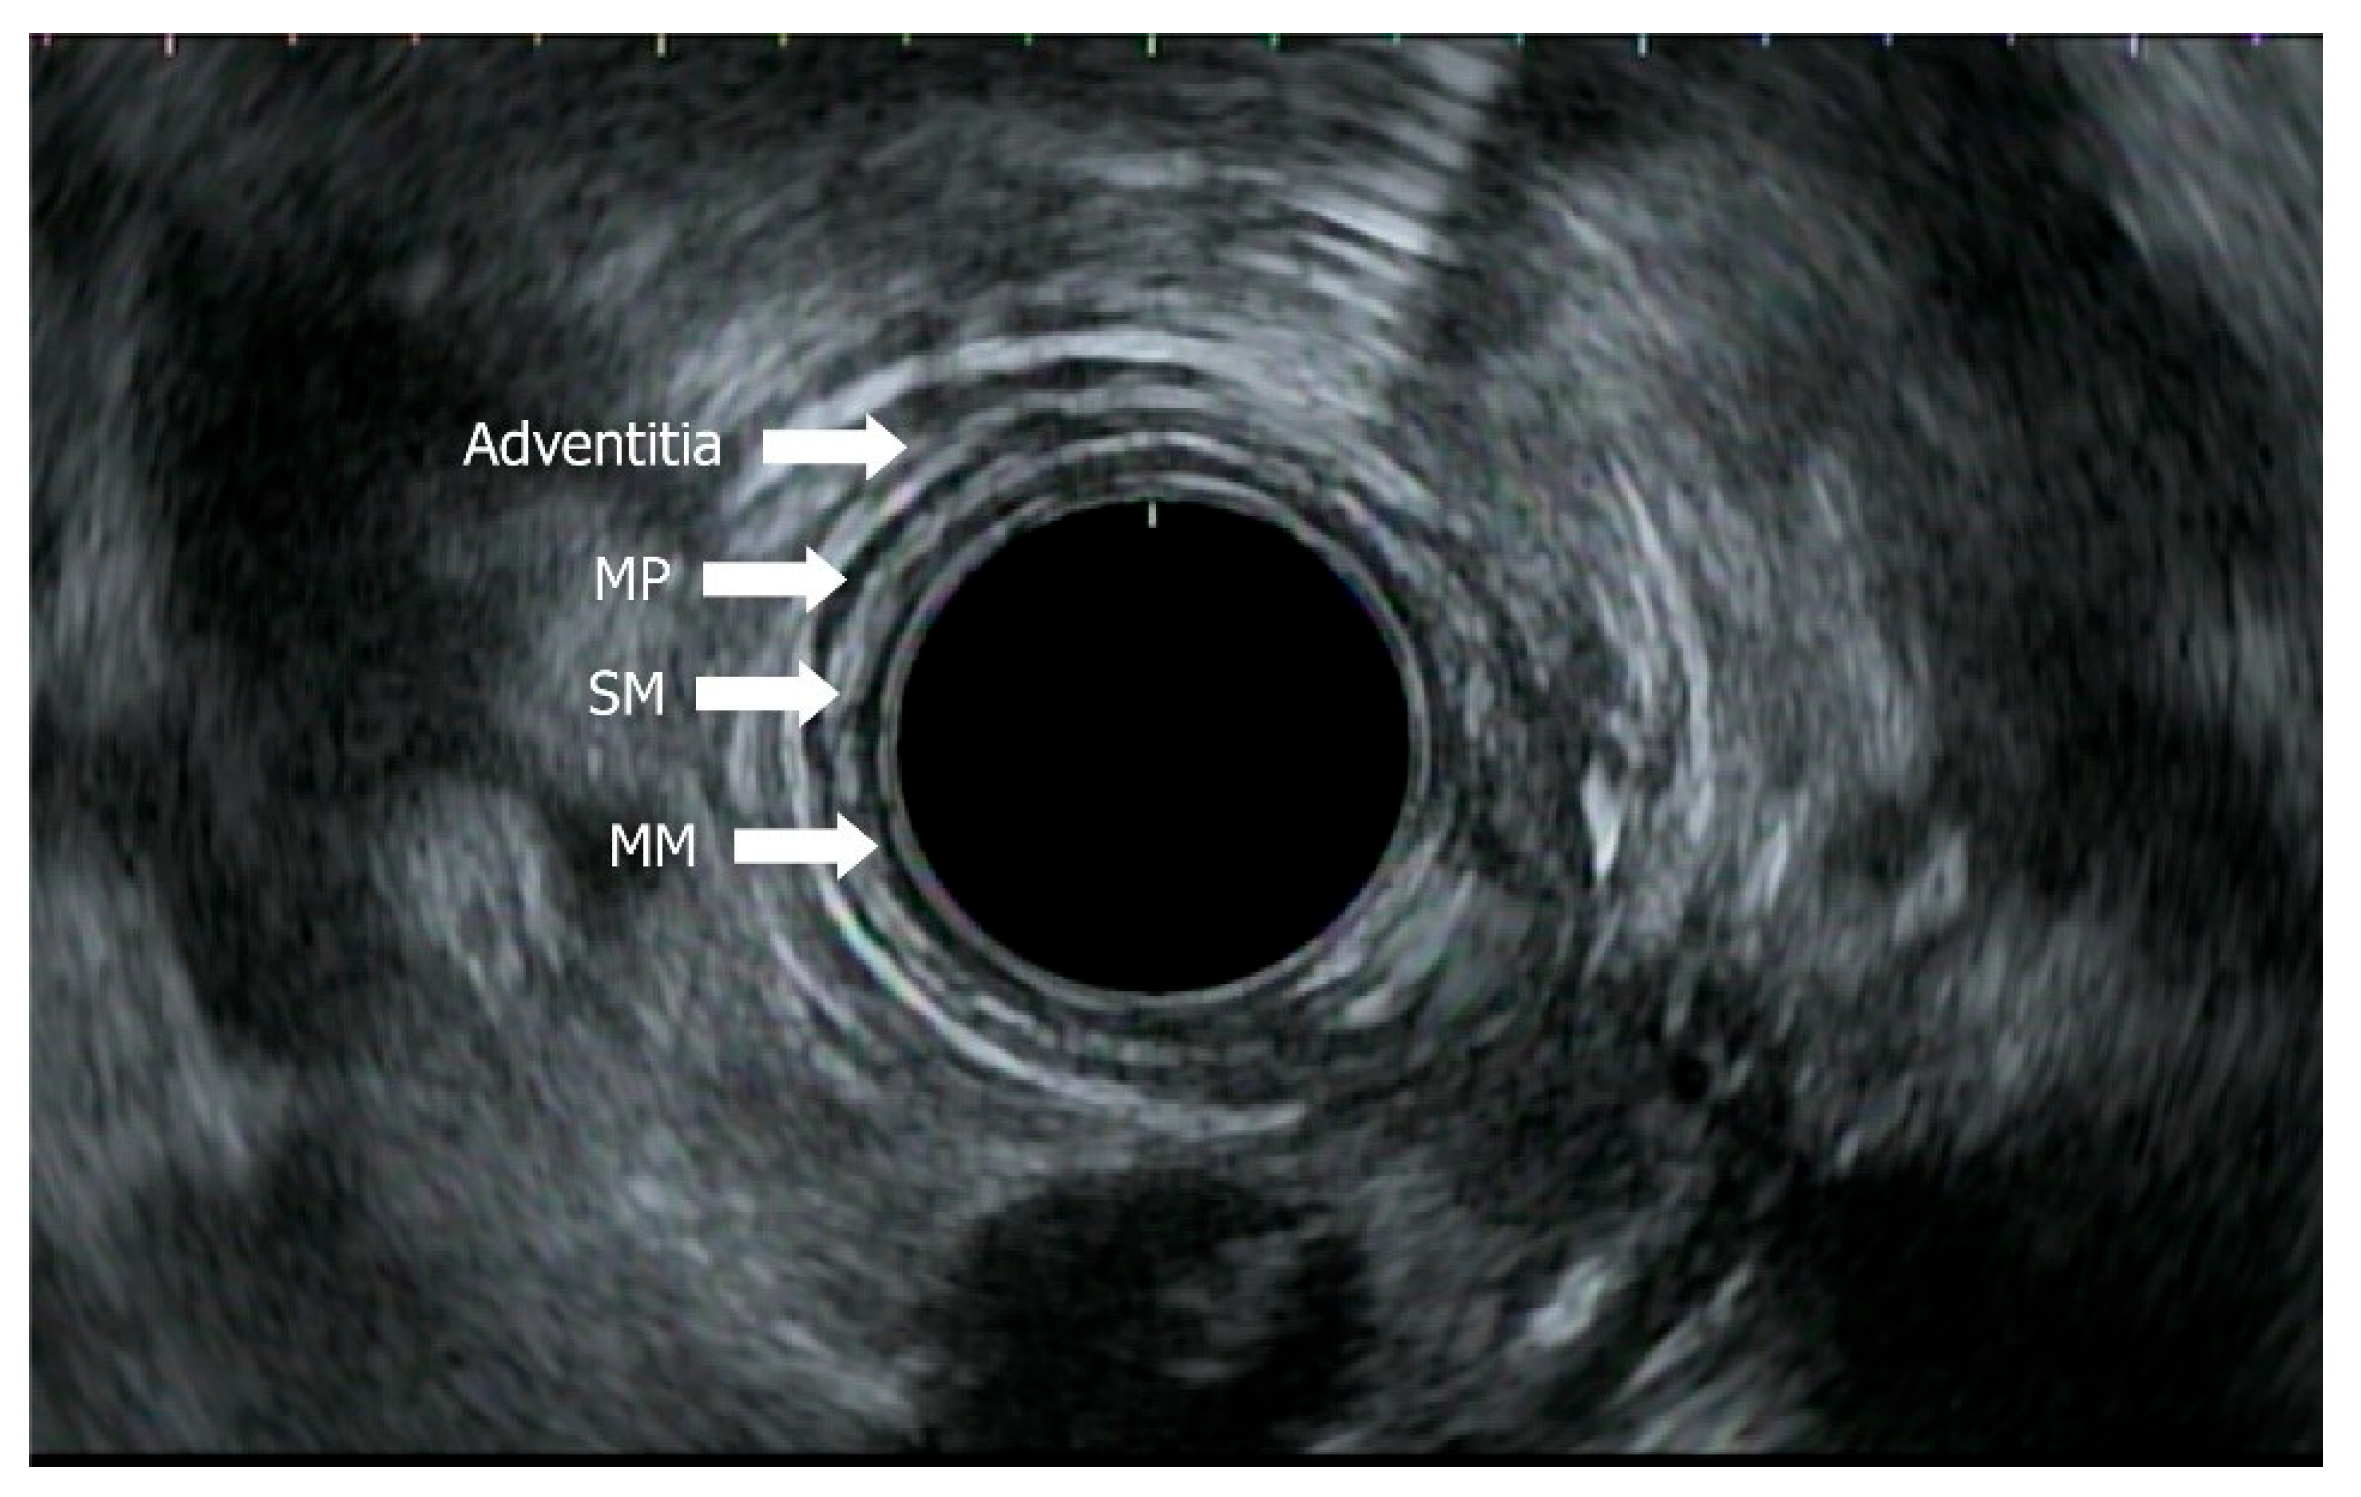

- Radlinski, M.; Shami, V.M. Role of endoscopic ultrasound in esophageal cancer. World J. Gastrointest. Endosc. 2022, 14, 205–214. [Google Scholar] [CrossRef]

- Thakkar, S.; Kaul, V. Endoscopic ultrasound staging of esophageal cancer. Gastroenterol. Hepatol. 2020, 16, 14–20. Available online: https://pubmed.ncbi.nlm.nih.gov/33867884/ (accessed on 29 May 2025).